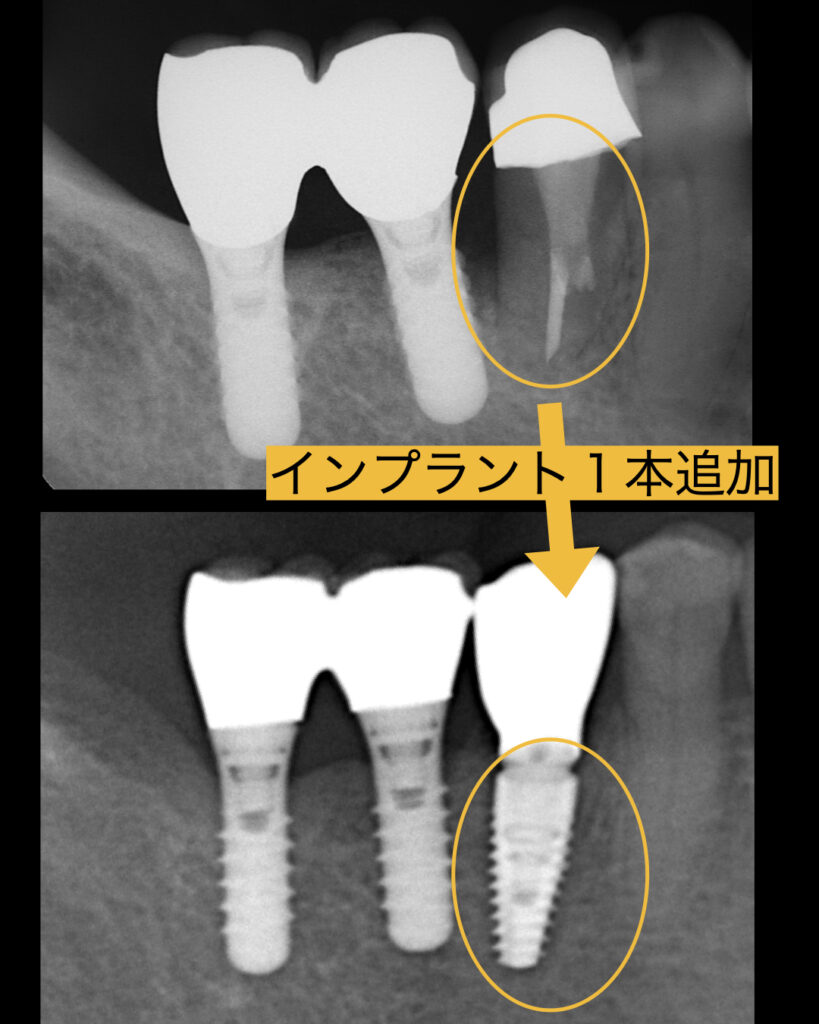

今回、歯茎が腫れてきたとのことで、見てみると歯牙が破折しており保存不可能であることお伝えしたところ、インプラントを希望され、歯を抜いてその日にインプラント入れる抜歯即時埋入を行うことになりました。

インプラント手術は抜歯に10分、インプラント埋入は15分ほどで終了しました。

問題は歯牙が破折し炎症が強かったので、少し骨のボリュームが少なくなっていました。

よって、歯を抜いてその日にインプラント埋入する、抜歯即時埋入、そして、同時に骨造成GBRを同時に行いました。術式としてはソケットシールと呼ばれる手法で骨補填材を入れたあと上部をレジンで封鎖する方法を選択しました。

痛みは全くなく、痛み止めは全く飲まなくよかったそうです。術後4ヶ月ほどで最終的なセラミックが入り患者様も大喜びでした。しかも16年前よりも手術が一瞬で終わり驚いていました。